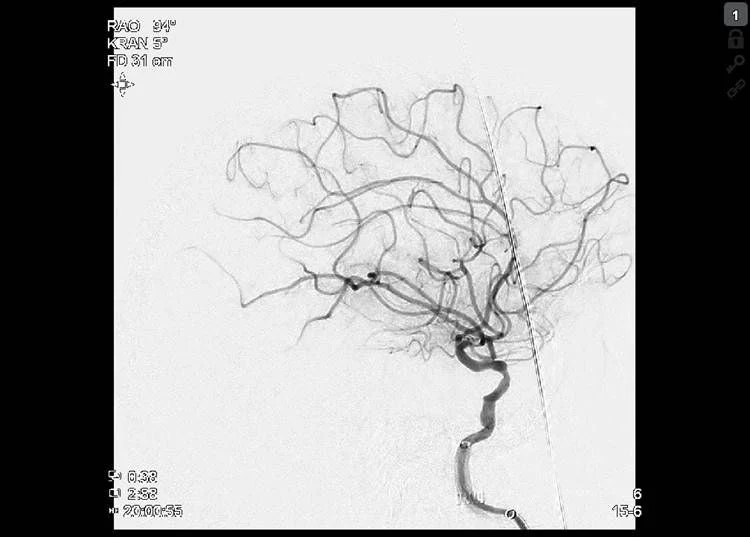

Thrombectomy was done with Embovac and Tigertriever (Rapid Medical) in general anaesthesia (door-to-groin 109 min, 19:44) with first pass recanalization TICI 2c in 16 min (20:00, door-to-final-TICI 123 min).